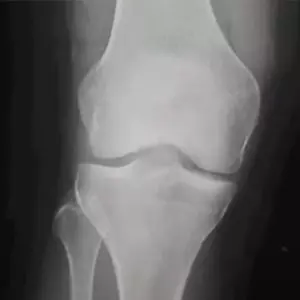

Evaluación médica y estudios de rodilla